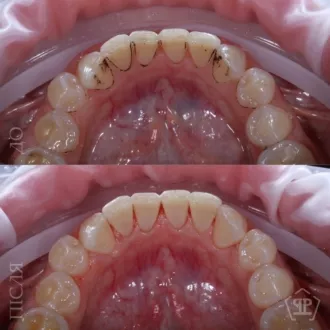

Комплексная гигиена зубов: гигиеническая чистка скейлером + аппаратом Air-Flow + полировка зубов профессиональной пастой